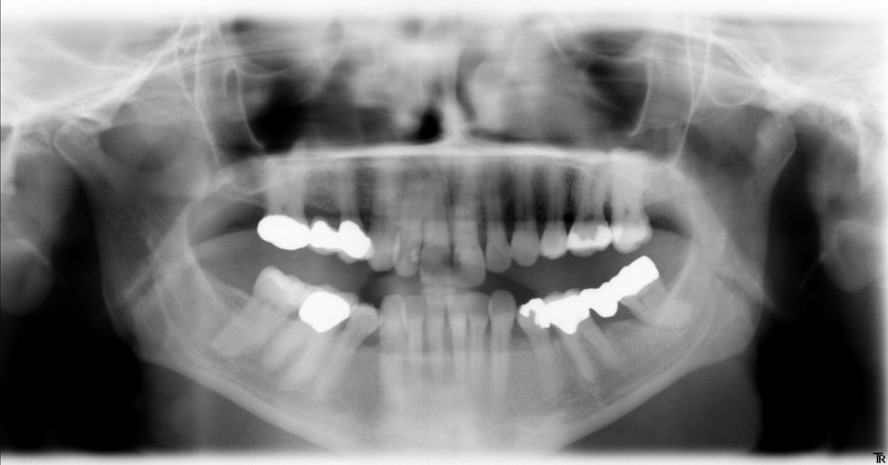

Eine Patientin, 44 Jahre, kam nach mehreren Jahren das erste Mal wieder in die Zahnarztpraxis. Sie klagte über bereits lang anhaltendes Zahnfleischbluten an den oberen Frontzähnen und den hinteren Backenzähnen, das sie selbst nicht wieder in den Griff bekam. Der Mundhygienestatus ergab folgendes Bild:

- Im gesamten Mundbereich war akkumulierte Plaque zu sehen.

- Zahnfleischtaschen von 6 bis zu 9mm an den Zähnen 11, 12, 15, 17, 21, 22, 26, 27 sowie 41, 45, 46, 48

- Außerdem wurde eine mikrobielle Diagnostik vorgenommen mit dem Ergebnis: Hoher Bakterienload und Anwesenheit von Porphyromonas gingivalis, Prevotella intermedia sowie Treponema denticola.

- Trotz des schweren bakteriellen Befalls lagen noch keine Zahnlockerungen und kein Furkationsbefall vor.

Abb.1: OPG der Patientin.

Die Patientin musste ab dem Zeitpunkt nur noch lernen, ihre häusliche Mundhygiene zu optimieren und ihre Ernährung auf ein bisschen mehr Obst und weniger Süßigkeiten umzustellen. Sie schaffte es. Als sie nach drei Monaten zum Recall kam, genoss sie ihr wieder gesundes Zahnfleisch. Es musste lediglich ein wenig Zahnstein entfernt werden. Nach sechs Monaten kam sie erneut zur Zahnsteinentfernung und einem erneuten PA-Screening. Sie war immer noch entzündungsfrei und der PSI-Index ergab nur noch Taschen von 2 oder 3mm. Ein weiteres halbes Jahr später wurde eine gründliche PZR durchgeführt und ein OPG gemacht. Auf dem Röntgenbild wird deutlich erkennbar, dass der Knochenabbau erfolgreich gestoppt werden konnte und die Taschentiefen reduziert wurden. Der Erfolg der Behandlung steht in einem optimalen Verhältnis zur finanziellen Investition und motiviert die Patientin sich weiterhin verantwortlich um ihre Mundgesundheit zu kümmern. Sie erscheint regelmäßig alle drei Monate zur Kontrolle.